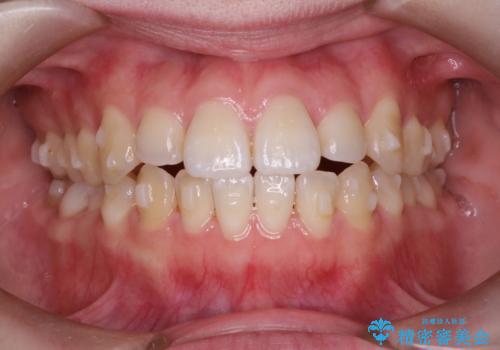

前歯がガタガタ・噛み切りにくい インビザラインによる歯を抜かない矯正

前歯にがたつきがあり、上下の歯が咬み合っていない状態でした。

歯列の横幅をひろげるのと、歯と歯の間をわずかに削ることにより、前歯のがたつきと、開咬を改善しました。